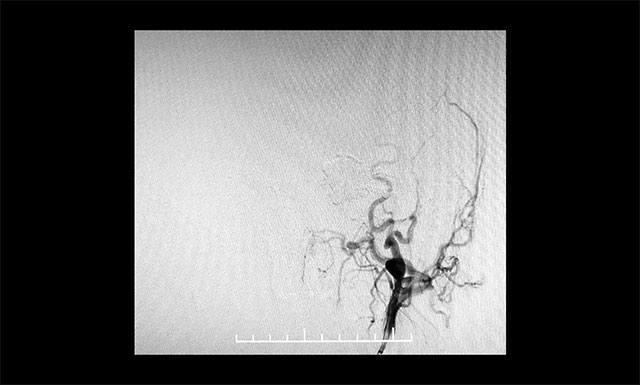

微導(dǎo)管造影確認(rèn)后,注入 Onyx 18膠7.5ml

▲ 微導(dǎo)管造影確認(rèn)后,注入 Onyx 18膠7.5ml